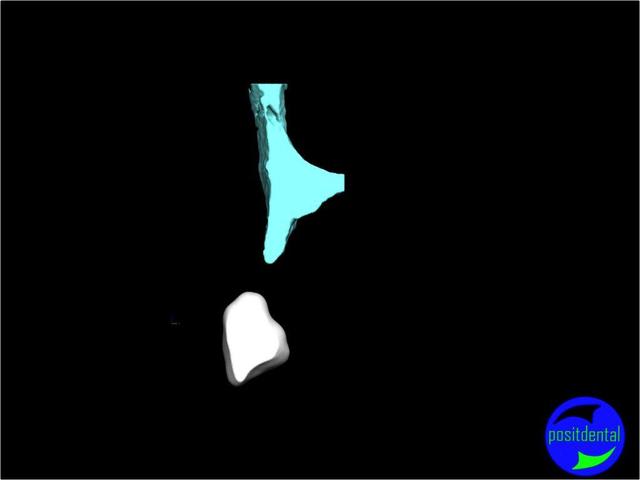

Posit fait une étude pour démontrer la faisabilité de son système, et honnêtement sa démarche semble intéressante, et provoque une réflexion sympa chez D57 et moi même.

La solution unique n'existant pas il est très intéressante que nous échangions nos différents points de vue.

La solution sera une expansion, (what else?) mais dirigée du point de vue prothésiste pour la partie mécanique, ce qui devrait être plus sécurisant pour le patient, et constructif pour nous tous.

une autre vue du photshopman:

modèle stéréo du à la gentillesse de Posit